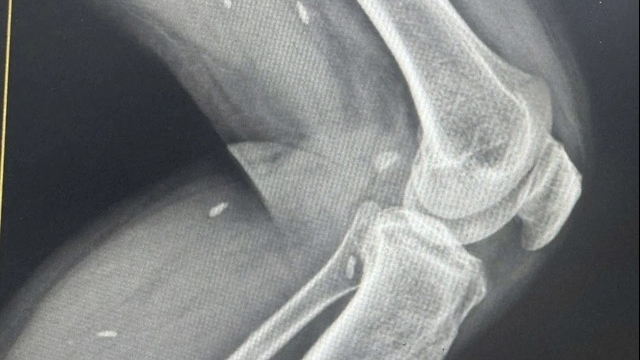

Mới đây, trên mạng xã hội facebook đã lan truyền một hình ảnh kèm theo lời chú thích: “Hình ảnh 2 bác sĩ phẫu thuật sau khi loại bỏ thành công các khối u não trong một cuộc phẫu thuật 32 giờ!”

Có lẽ vì đã trải qua 32 giờ căng thẳng với một ca phẫu thuật khó “u não” đã khiến 2 bác sĩ này “hết sức”. Ngay sau khi ca phẫu thuật kết thúc thành công, họ nằm luôn xuống nền đất mà nghỉ ngơi, không kịp thay bỏ trang phục. Lúc này, họ đã quá mệt mỏi để nghĩ đến những điều khác.

Sau 32 tiếng “căng não” chiến đấu vì sức khỏe của bệnh nhân, sau khi thành công họ mới thấy mình mệt và lả xuống. Thậm chí một bác sĩ vẫn cố giơ tay tạo dáng khiến người xem vừa thương vừa thích thú với sự đáng yêu này.